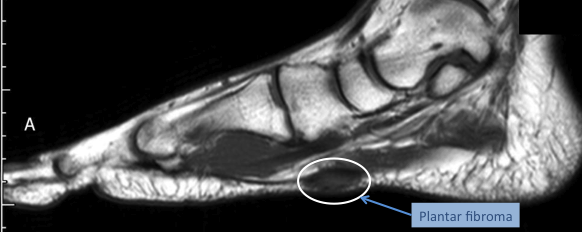

18. 족저섬유종증(Plantar fibromatosis)이란 무엇인가?

환자는 무게 부하가 주어질 때 통증이 존재하고 족저근막의 경로를 따라서 촉진할 수 있는 두꺼워진 결절을 가진다. 족저섬유종증(Plantar fibromatosis)은 환자의 10~40%가 양측성일 수 있으며, 모든 연령층에서 발생할 수 있는데, 남성이 여성보다 두 배 정도 더 발생한다. T1 강조 영상에서는 병변이 저음영이거나 근육과 동일한 음영일 수 있다. T2 강조 영상에서는 병변이 저음영이거나 약간 고음영일 수 있다. 이러한 병변은 가돌리늄 조영으로 강조되고 대개 밝게 나타난다.

△ 족저섬유종 (Plantar fibroma)

(이미지 출처 : http://www.foothealthfacts.org/footankleinfo/Plantar_Fibroma.htm)​

△ 족저섬유종증 (Plantar fibromatosis) MRI

(이미지 출처 : http://www.lfaclinic.co.uk/conditions/plantar-fibroma-and-plantar-fibromatosis/)